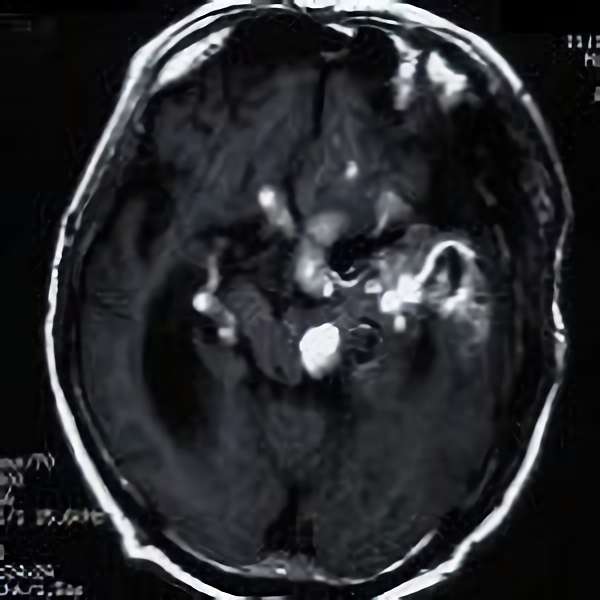

手術後